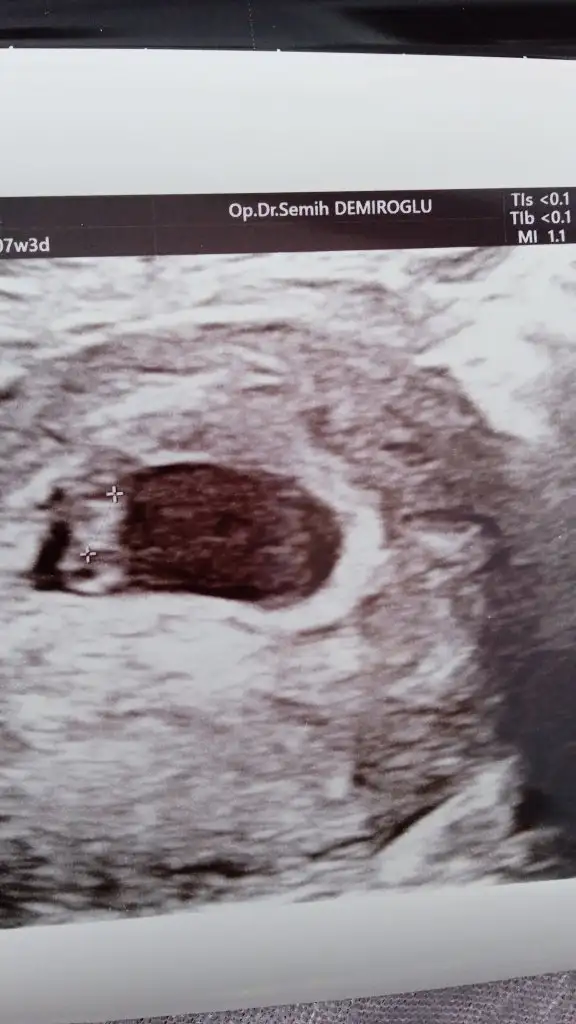

Ben de bir tahmin rica edeceğim :)) 7 haftalık